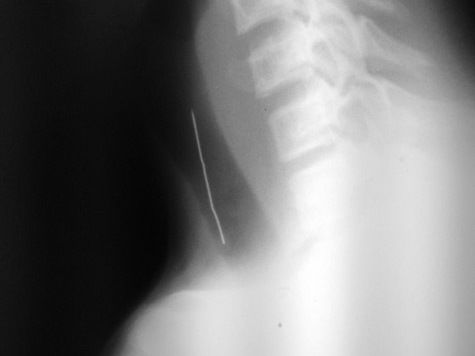

- Доктора искали иголку в горле пациента

| Доктора искали иголку в горле пациента Posted: 08 Oct 2013 10:45 AM PDT С довольно необычным случаем столкнулись медики из МОНИКИ им. М.Ф. Владимирского This posting includes an audio/video/photo media file: Download Now |